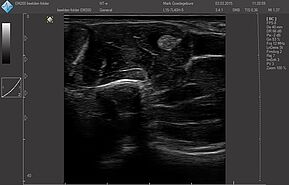

Области исследований:

- Щитовидная железа

- Молочная железа

Система УЗИ поддерживает широкий диапазон трансдюсера нового поколения: монокристаллические, с элементами высокой плотности, широкополОсными и многочастотными от 1,0 МГц до 18,0 МГц:

Датчики имеют большую чувствительность и высокое разрешение, благодаря чему обеспечивают максимальное проникновение и улучшают соотношение сигнал /шум. В результате формируется максимально четкая детализированная картинка УЗИ изображения.